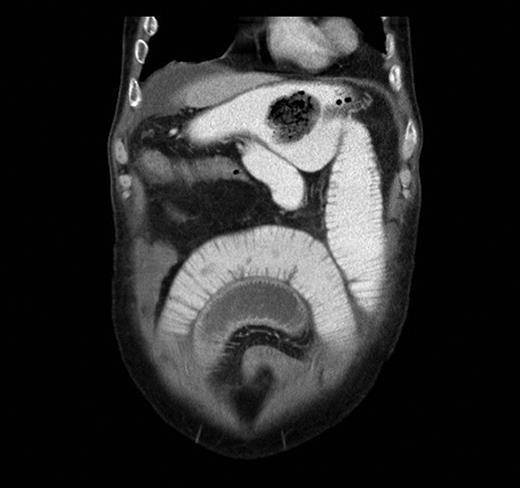

A contrast-enhanced CT scan was arranged and it showed features of SBO with collapse of the terminal ileum. There was evidence of a previous gastrojejunostomy with suspected foreign bodies in the stomach and proximal ileum. (Figs 1 and 2) .

Sagittal CT scan view showing foreign bodies in the stomach and the ileum with transition point in the small bowel.